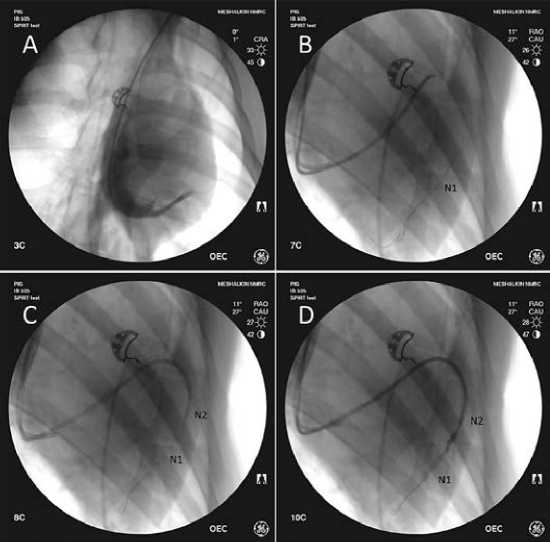

Рис. 2. Этапы установки баллонных катетеров, данные флюороскопии:

А – катетеризация и контрастирование коронарного синуса;

B – проведение баллона N2 в дистальный сегмент вены на проводнике;

C – установка баллона N1;

D – контрольное контрастирование через баллон N1 для контроля рефлюкса;

N1 – дистальный баллонный катетер;

N2 – проксимальный баллонный катетер

Под контролем рентгеноскопии в выбранную коронарную вену на гидрофильном проводнике 0,014 дюйма проводили баллонный катетер («дистальный баллон»). Затем через дистальный интродьюсер аналогичным образом устанавливали второй катетер («проксимальный баллон») (рис. 1).